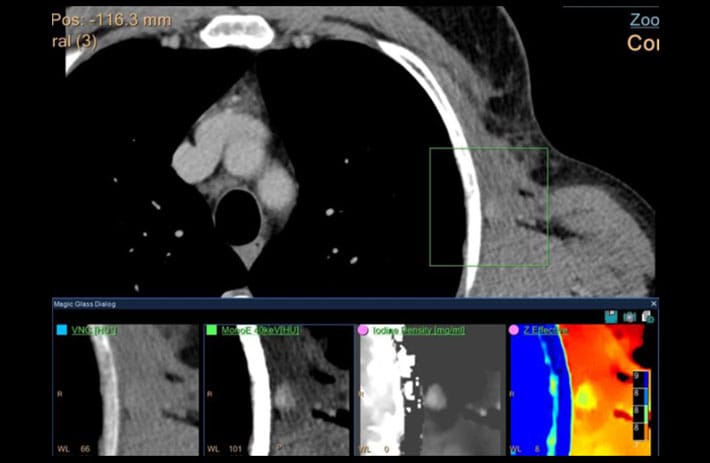

Mit dem Spektral-Detektor-CT werden Spektraldaten automatisch bei jedem Scan erfasst. Die Informationen stehen jederzeit auf der Scankonsole, der CT-Workstation sowie an jedem PACS-Arbeitsplatz zur Verfügung, sodass es nicht notwendig ist, den Patienten erneut zu scannen, bspw. wenn initial zufällige Anomalien festgestellt wurden. Dadurch profitieren Anwender durch eine höhere Diagnosesicherheit und weniger Nachuntersuchungen auf anderen bildgebenden Systemen. Unsere Fallsammlung zeigt, welchen klinischen Mehrwert der Spektral-Detektor-CT in unterschiedlichsten Anwendungsbereichen in der klinischen Routine bringt. Jede Woche gehen neue Fälle live.